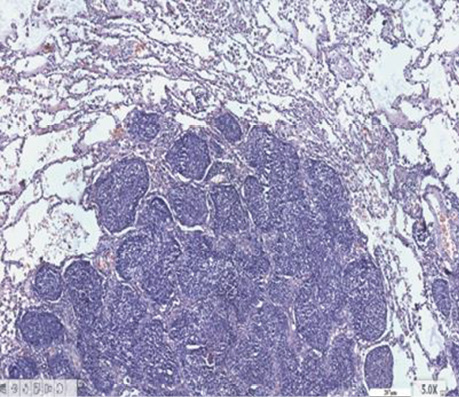

У гістологічній структурі залозистого раку виявлялися солідні ділянки росту аденокарциноми з ознаками різного ступеня диференціювання. Ідентифікувалися ділянки БАРЛ, де можна було фіксувати його ріст в альвеолах. Прослідковувалися великі альвеоли з чітко визначеним ростом РЛ в них, які заповнювали всю альвеолу з некрозом у центрі (рис. 3–6).

Рис. 3. Залозистий рак. Ріст у множинних альвеолах. Гематоксилін і еозин. Збільшення ×200